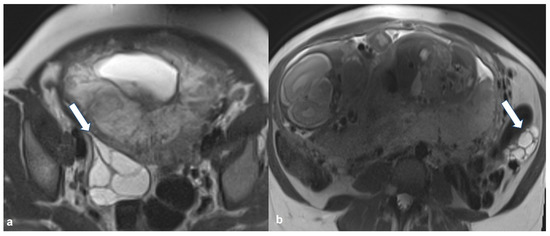

2.5.2. Decidualized Endometrioma

2.5.3. Epithelial Ovarian Cancer